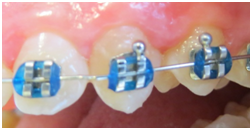

From a total of 12 screened participants, lesions .The patients were reexamined at three and six months. Nyvad Scores 1:112 faces (83,6%); 2=14 faces (10,4%); 3 =6 faces (4,5%); 5 =2 faces (1,5%). The active white spots, were more frequent in score 1, when compared to scores 2, 3 and 5, significant at 1%. Score 2, had significative differences towards score 5. The active white spots, were more frequent in score 1, when compared to scores 2, 3 and 5, significant at 1%. Score 2, had significative differences towards score 5 (Table 1). After three month, from the 134 white spot lesions, the majority of them inactivated 130 (97,01%), became inactive, while 4 remain active. The scores achieved after three month remain stable till one year evaluation (Table 2). Figure 1 & 2 shows clinical differences before and after the use of a raging on 4 week uses consecutively tooth mousse in orthodontic treatment, during treatment (Figure 3A & 3B), and after orthodontic treatment (Figure 4A & 4B).

Figure 3B Lucas after three month 4 weeks TM.

Figure 4B Angelica one year after 4 weeks tooth mousse.